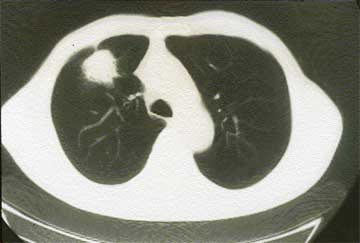

悪性中皮腫の診断は、レントゲン写真やCTや超音波写真の後に行われる、胸水や腹水の穿刺のよる細胞診断、その後の胸腔鏡や腹腔鏡等による組織診断に基づいて行われます。

(写真 悪性胸膜中皮腫CT像)

複数の免疫染色により、肺癌やその他の癌の転移との区別がつけやすくなってきました。但し胸水や腹水の出現時に悪性所見を呈さない例もあり、診断まで数ヶ月以上かかる事がやむをえない場合もある、診断の難しい疾患である事は今も変わりはありません。2018年の中皮腫について詳しく知りたい方は、当HP内の「中皮腫」をご覧ください。この病気について詳しくお知りになりたい方は、ひまわり診療所HP をご覧ください。